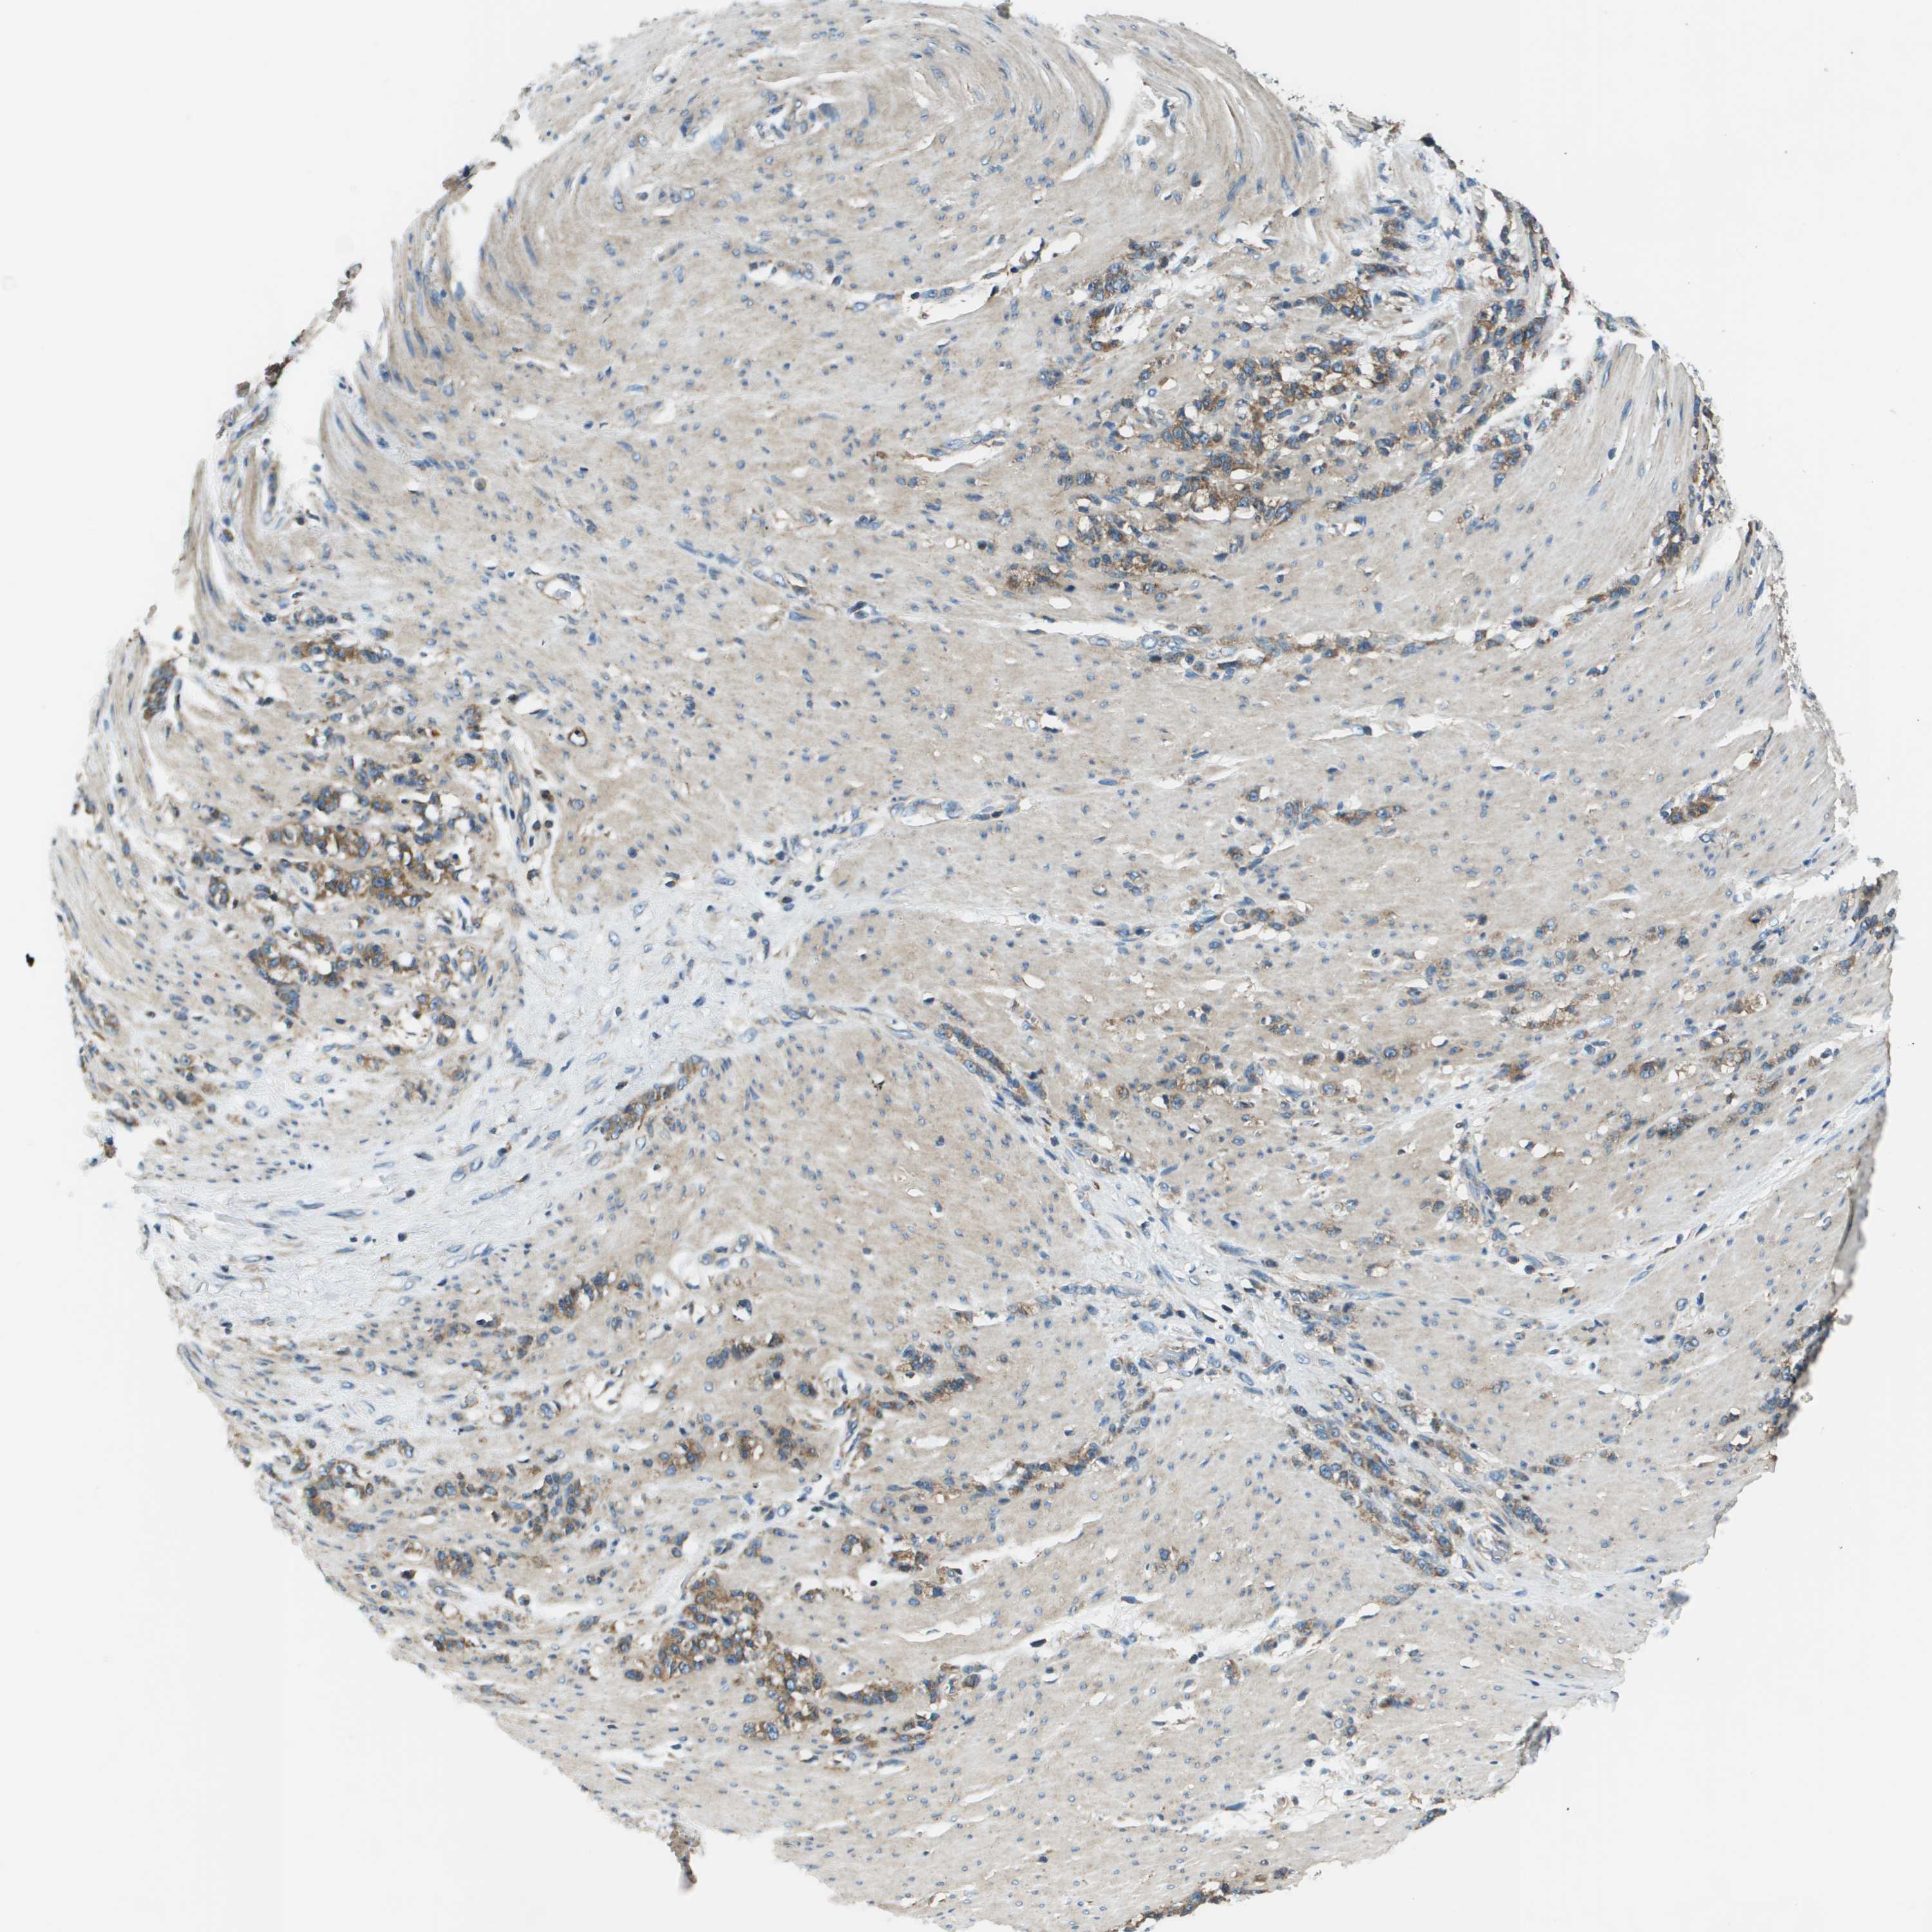

STOMACH CANCER - Protein expressioni

A mouse-over function shows sample information and annotation data. Click on an image to view it in a full screen mode. Samples can be filtered based on level of antibody staining by selecting one or several of the following categories: high, medium, low and not detected. The assay and annotation is described here.

Note that samples used for immunohistochemistry by the Human Protein Atlas do not correspond to samples in the TCGA dataset.

Antibody stainingi

Antibody staining in the annotated cell types in the current human tissue is reported as not detected, low, medium, or high, based on conventional immunohistochemistry profiling in selected tissues. This score is based on the combination of the staining intensity and fraction of stained cells.

Each image is clickable and will lead to virtual microscopy that enables deeper exploration of all samples and also displays staining intensity scores, fraction scores and subcellular localization as well as patient and tissue information for each sample.

Antibody HPA014547

Staining

High

Medium

Low

Not detected

Intensity

Strong

Moderate

Weak

Negative

Quantity

>75%

75%-25%

<25%

None

Location

Nuclear

Cytoplasmic/membranous

Cytoplasmic/membranous,nuclear

Adenocarcinoma, NOS